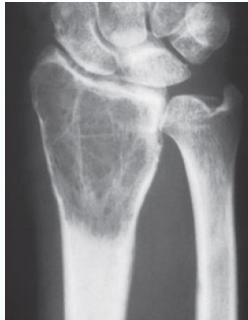

Giant-Cell Tumor

- Unknown origin:

- Giant cells abundant

- Behavior:

- One third benign

- One third locally aggressive

- One third (less) with distant metastasis

- Young adults

- Common sites:

- Around knee

- Proximal humerus

- Distal radius

Radiological Features

- Eccentric lesion:

- Radiolucent

- Soap bubble

- Abuts (adjacent) against the joint

- Thin cortex

- Margins may be clear / unclear:

- Depends on aggressiveness

- Treatment:

- Curettage & bone grafting

- More wide excision in recurrent and aggressive lesions